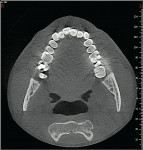

Many CBCT units have a variable FOV that allows the clinician to limit the radiation exposure to the region of interest. The limiting factor is the size of the image detector, which varies depending on the manufacturer, but for the sake of simplicity, this article will discuss them in categories—small (< 6 in), medium (6 in), large (9 in), and extra-large (12 in) FOVs (Figure 2 and Figure 3). The maximum image of a small FOV usually can accommodate several teeth or a sextant of an arch. The maximum medium FOV can accommodate the normal adult dentition, and the maximum large FOV encompasses the maxillofacial anatomy including the condyles and most of the orbits. Finally, the extra-large FOV can accommodate the full skull in most cases. Regardless of the volume capacity of the unit, it is important to restrict the FOV to the region of interest, which has a significant effect on the amount of radiation absorbed.23

It is important to note that the various CBCT units come with standard viewing software, which will allow the dentist to examine the selected area of interest in all three planes: axial, coronal, and sagittal (Figure 5).